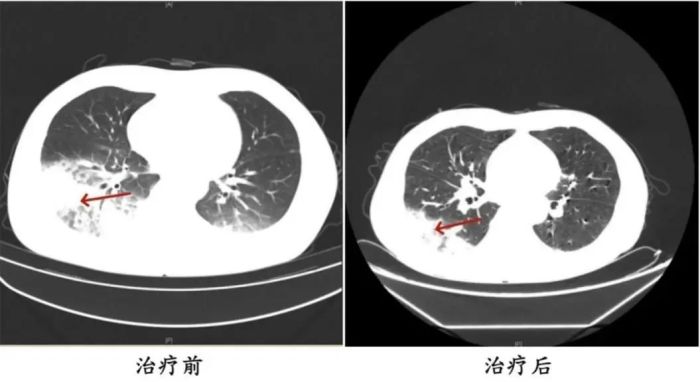

家人见状,立即将他送医。胸部CT显示李先生的左肺已出现大面积白色影像,几乎占据一半肺部。经过检测,最终确认是嗜肺军团菌肺炎

李先生肺部治疗前与治疗后的对比